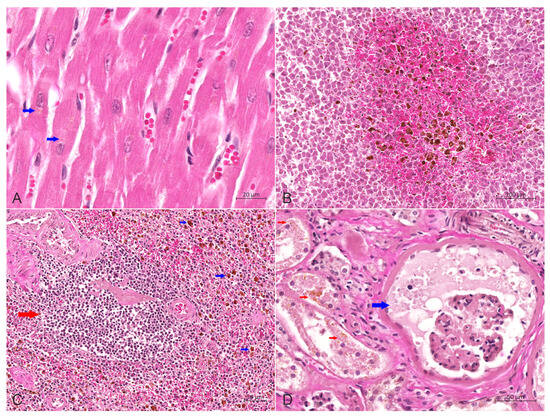

Furthermore, mild congestion and dilation of the small blood vessels in the myocardial interstitium were seen, with a demonstrable deposition of brownish yellow lipofuscin particles in the cytoplasm of myocardial cells (Figure 5A). Kupffer cells in the liver were widely activated and proliferated, engulfing many hemosiderin-containing particles. Severe congestion and a hemorrhage around the central vein were observed in the middle lobe of the liver (Figure 5B). The number of lymphocytes in the spleen was significantly reduced, and the volume of white pulp was small. Iron-swallowing cells were widely distributed in the red pulp, with apoptotic lymphocytes visible (Figure 5C). The histopathological changes in the kidneys were characterized by chronic sclerosing glomerulonephritis, diffuse fibrosis in the renal cortex, evident hyperplasia of the glomerular capsule and the surrounding connective tissue and complete fibrosis of the entire glomerulus in severe areas. The residual renal tubular epithelial cells were swollen and exhibited slight to moderate steatosis, and scattered or more abundant lipofuscin particles could be seen in the cytoplasm (Figure 5D). The walls and villi of the small intestine were thinner than usual. Other findings included edema and interstitial connective tissue hyperplasia of the adrenal gland.

Figure 5. Hematoxylin-eosin stain of heart, liver, spleen and kidneys. (A) Slight congestion and dilation of the small blood vessels in the myocardial interstitium were observed, with a small amount of brownish yellow lipofuscin particles (red arrow) in the cytoplasm of myocardial cells, bar = 20 μm. (B) The central area of the liver lobules was significantly congested, and the activation and proliferation of Kupffer cells containing hemosiderin were increased, bar = 100 μm. (C) The number of lymphocytes in the spleen was reduced considerably, and the volume of white pulp (red arrow) was decreased. Also, macrophages containing hemosiderin (blue arrow) were dispersed in the red pulp, bar = 50 μm. (D) Wide renal fibrosis was seen, with the extensive proliferation of connective tissue around some glomeruli, dilation of renal sacs filled with protein-rich urine (blue arrow), degeneration of renal tubular epithelial cells, and noticeable lipofuscin particles (red arrow) in the cytoplasm, bar = 50 μm.